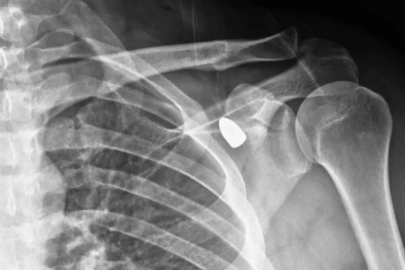

Konya’da yaşayan okul müdürü Celal Şenyiğit’in koluna 6 yıl önce yorgun mermi saplandı. Ancak merminin bulunduğu yer riskli bölge olduğu için çıkarılamadı. Aradan geçen 6 yılın ardından okul müdürünün omzundaki mermi kendiliğinden yer değiştirince operasyon imkanı doğdu.

Konya’da okul müdürü Celal Şenyiğit altı yıl önce çay ocağında otururken omzuna yorgun mermi isabet etti. Ancak yapılan muayenelerde merminin yeri nedeniyle hareket kaybı riski taşıdığı tespit edilince herhangi bir operasyon yapılmadı.

6 yıl boyunca omzundaki mermi ile yaşayan Şenyiğit, ağrı ve sertlik şikayetiyle Akşehir Devlet Hastanesine başvurdu. Yapılan muayenelerde koltuk altındaki kitlenin, omzuna saplanan yorgun mermi olduğu tespit edildi. Mermi, gerçekleştirilen operasyonla çıkarıldı. Şenyiğit, olayla ilgili şikayetçi olduğunu, çıkarılan merminin incelemeye gönderildiğini söyledi.